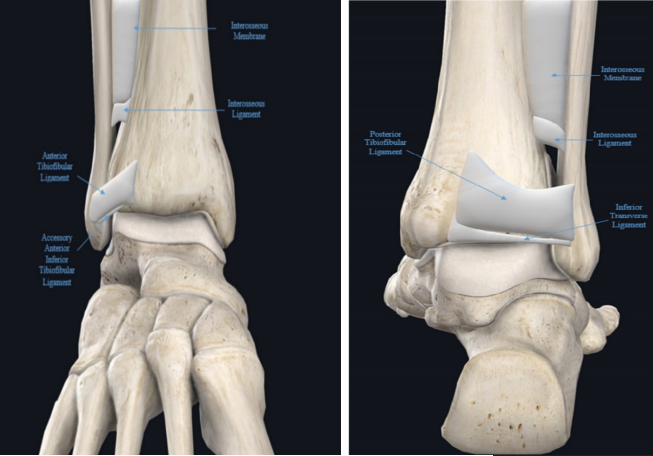

踝关节是胫腓骨远端形成的踝穴,并通过内、外侧两组韧带与距骨构成,下胫腓韧带复合体是踝穴的重要组成结构,连接胫腓骨,在解剖结构和维持功能方面起着重要作用。下胫腓联合包括胫腓骨远端和下胫腓联合韧带复合体。下胫腓联合韧带复合体由四条韧带组成,包括下胫腓前韧带、下胫腓后韧带、下胫腓横韧带和骨间韧带。在组成下胫腓联合复合体的诸韧带中下胫腓横韧带是最长的韧带,最宽的韧带是下胫腓骨间韧带,最厚的是下胫腓后韧带。下胫腓关节是一个微动关节,生理状态时可随着踝关节运动而出现旋转和平移的复合运动,包括上下、前后、旋转及侧方运动。踝关节骨折合并下胫腓联合损伤通常发生在旋前外旋、旋后外旋和旋前外展型损伤,其中以旋前外旋伴有下胫腓损伤最为常见。